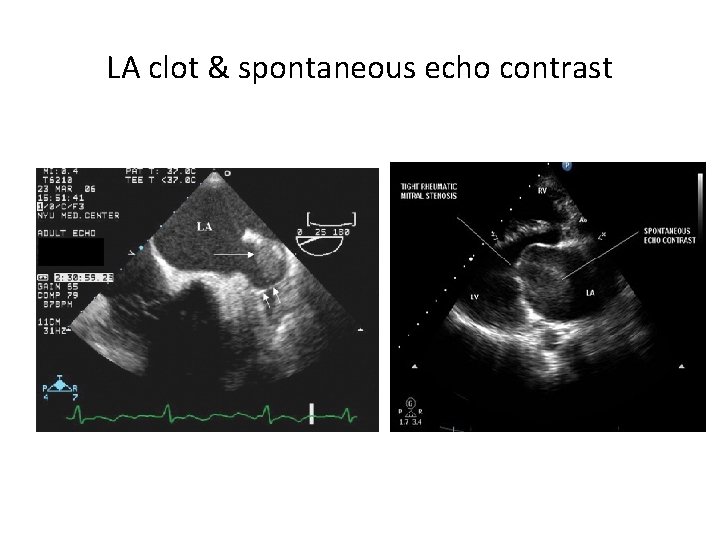

Secondary features of MS • Mainly due to elevated LA pressure. • LA and LA appendage dilation occurs. • Increased chance for thrombus formation due to blood stasis. • Dilated RA , RV and paradoxical septal motion may be seen due to pulmonary hypertension.

LA clot & spontaneous echo contrast